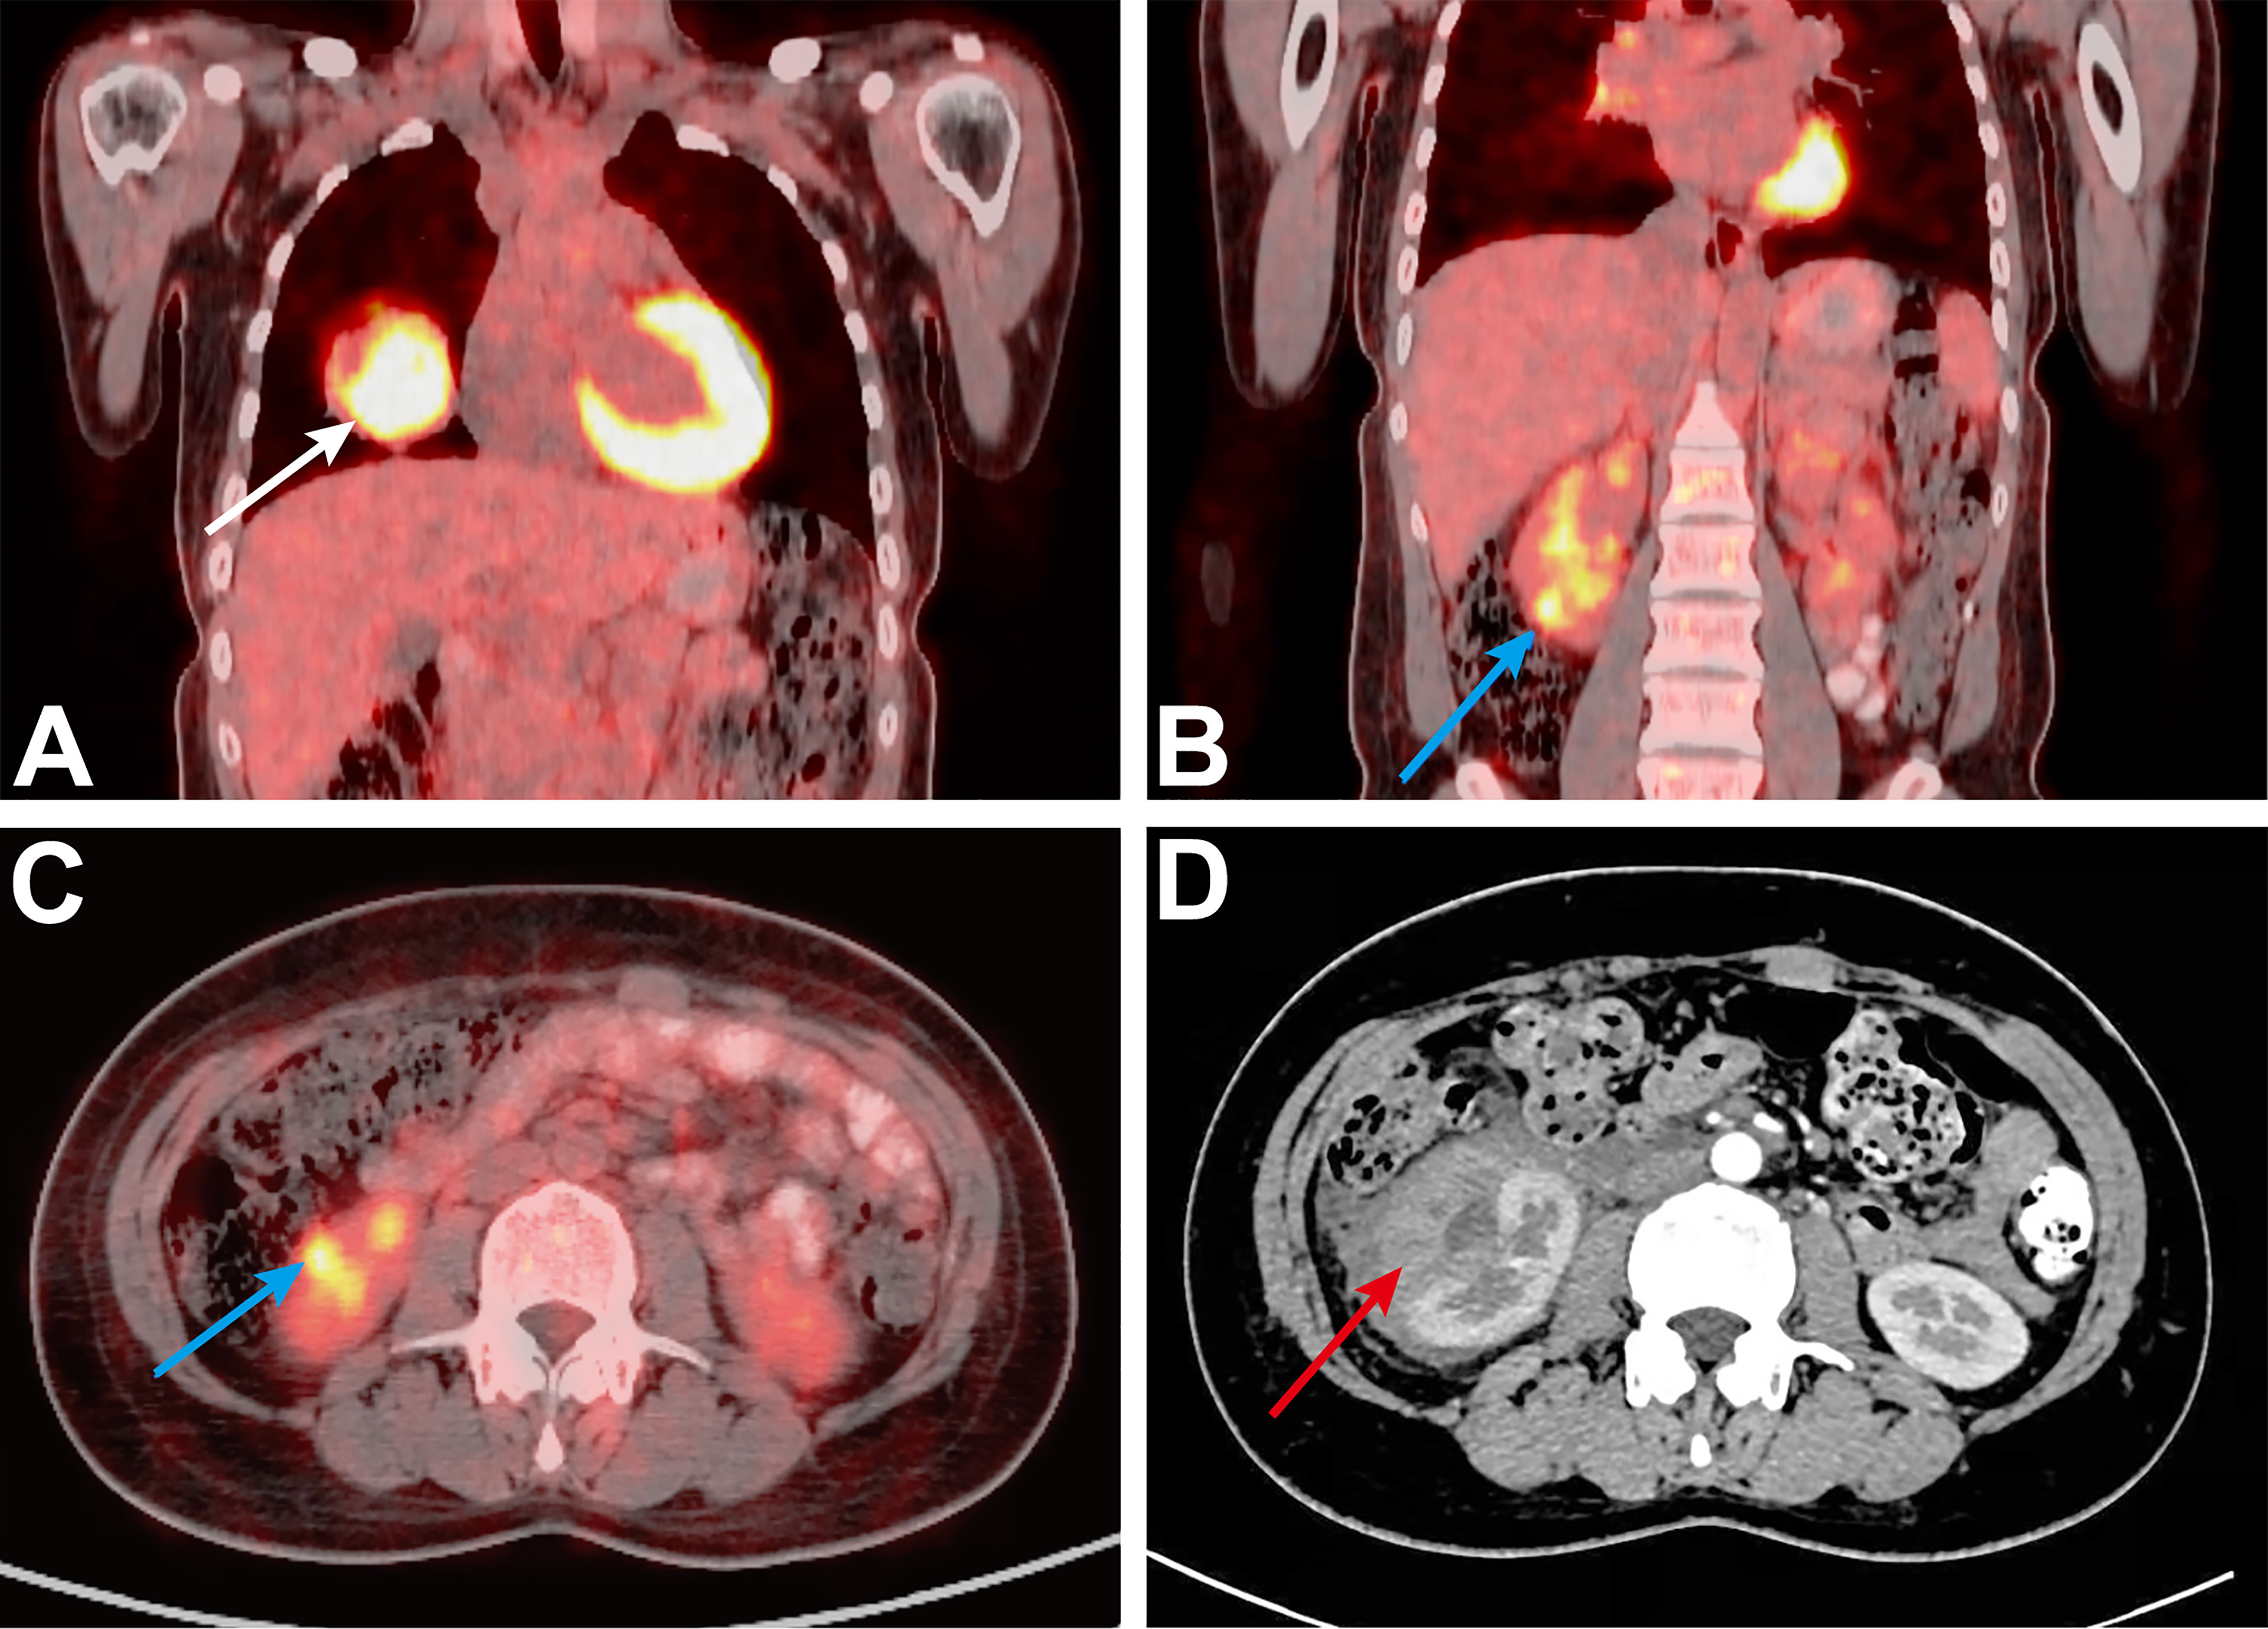

![Value of [68Ga]Ga-NYM046 PET/CT, in Comparison with 18F-FDG PET/CT, for ...](https://jnm.snmjournals.org/content/jnumed/65/12/1884/F6.large.jpg)

![Value of [68Ga]Ga-NYM046 PET/CT, in Comparison with 18F-FDG PET/CT, for ...](https://jnm.snmjournals.org/content/jnumed/65/12/1884/F5.large.jpg)